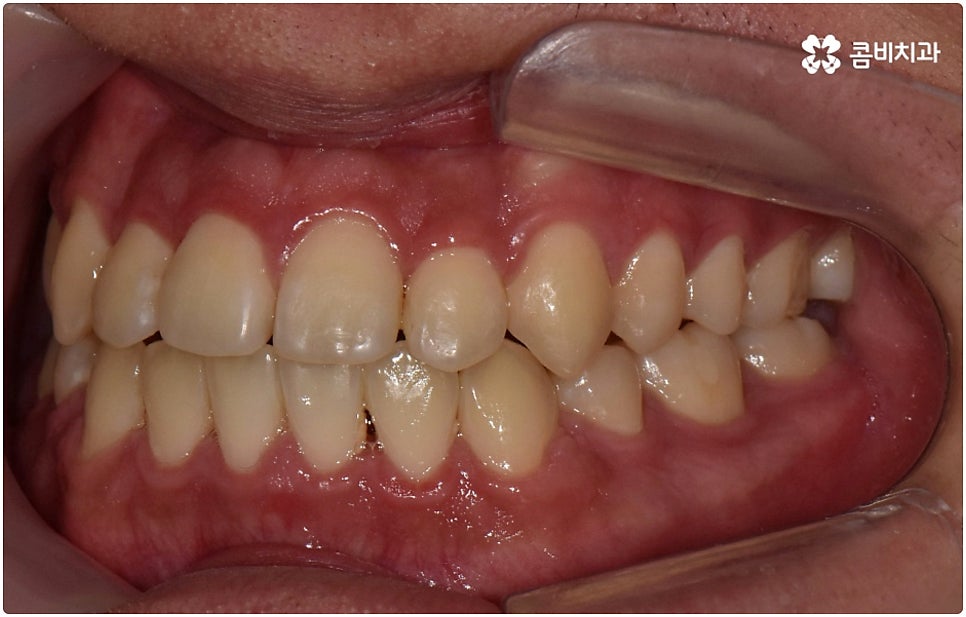

부정교합은 부정교합 1급, 부정교합 2급, 부정교합 3급 이렇게 세가지 종류로 나눌 수 있는데요. 부정교합 1급은 이를 다물었을 때 위아래 어금니는 잘 맞물리지만 덧니가 있거나 치아 사이가 살짝 벌어져 있는 경우처럼 치열이 삐뚤어진 경우를 말하는 것으로 골격이나 구조적인 부분에는 크게 문제가 없기 때문에 정도가 심하지 않다면 보다 빠르고 간편한 교정 치료가 가능한 케이스라고 할 수 있어요. 부정교합 2급은 상악이 하악보다 더 튀어나온 상태로 위에서 언급했던 무턱, 돌출입이 여기에 속하며 반대로 부정교합 3급 은 주걱턱처럼 하악이 상악보다 튀어나온 상태를 의미하고 있습니다.

부정교합 2급, 부정교합 3급 과 같이 구조적인 부분에 원인이 있는 문제라면 잇몸뼈가 다 굳고 난 다음인 중장년 성인분들의 경우 교정 치료를 받는 것이 과연 부정교합 개선에 효과가 있을까 궁금해 하실 수 있어요. 특히 턱관절 이상 문제는 수술을 통해서만 고칠 수 있다고 알고 계셨던 분들은 부담을 느끼고 치료를 미루셨을 수 있는데요. 물론 성인분들의 경우 상황에 따라, 예를 들어 정도가 매우 심한 부정교합 3급 케이스라면 악교정수술을 받아야 할 수도 있습니다. 또한 대부분의 부정교합 2급, 부정교합 3급 케이스들 같은 경우 초등학교 고학년에서 중학교 저학년 사이에 교정 치료를 시작하는 것이 좋다고 권유하는 것도 사실인데요, 그 이유는 아무래도 치아 이동 속도가 빠르고 전반적인 발달 상황에 맞추어 자연스럽게 치료를 진행할 수 있는 성장기의 특성상 이 시기부터 지속적으로 턱뼈 크기 부조화를 조절하고 상하악의 올바른 성장을 유도하는 게 보다 효율적이기 때문이라고 할 수 있어요.